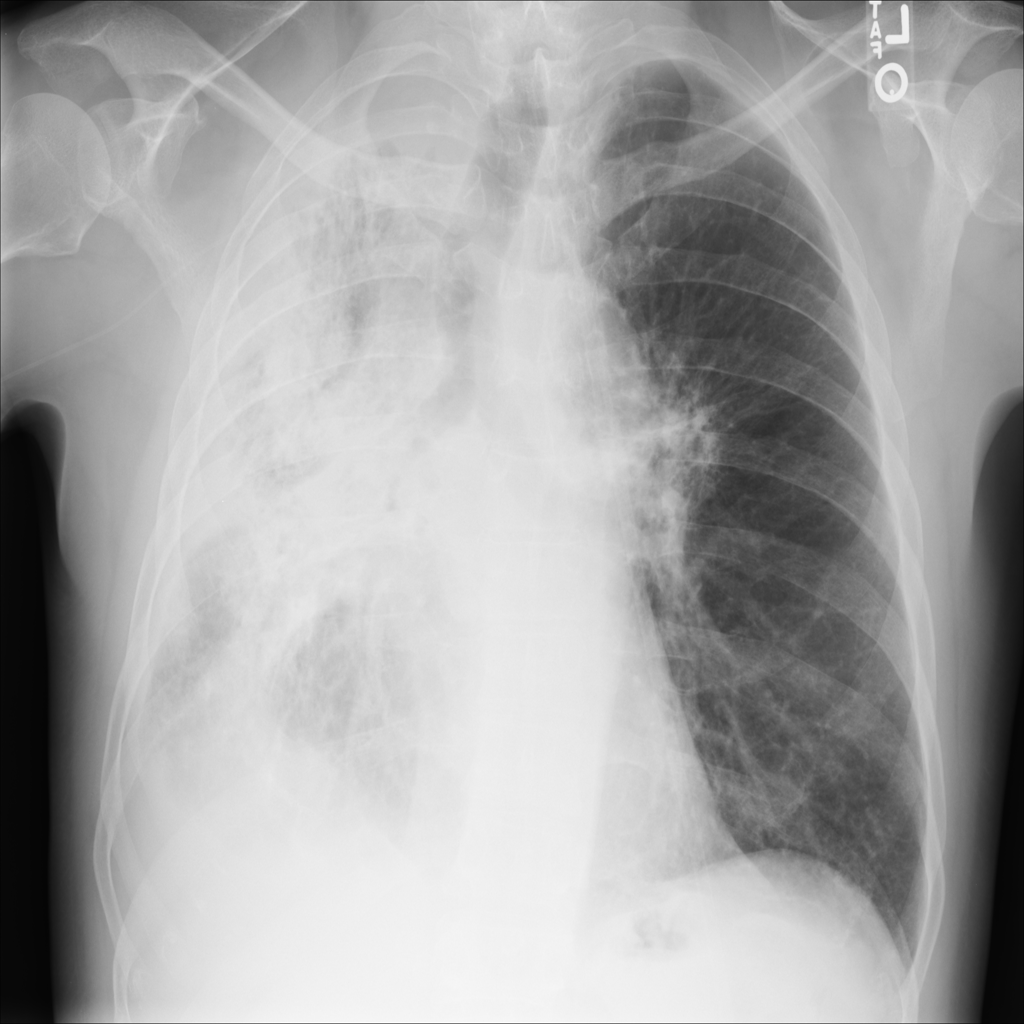

Showing up to 90 reference images for Pneumonia.

PAT-EBE1 · IMG-019Pneumonia

PAT-EBE1 · IMG-019

AP